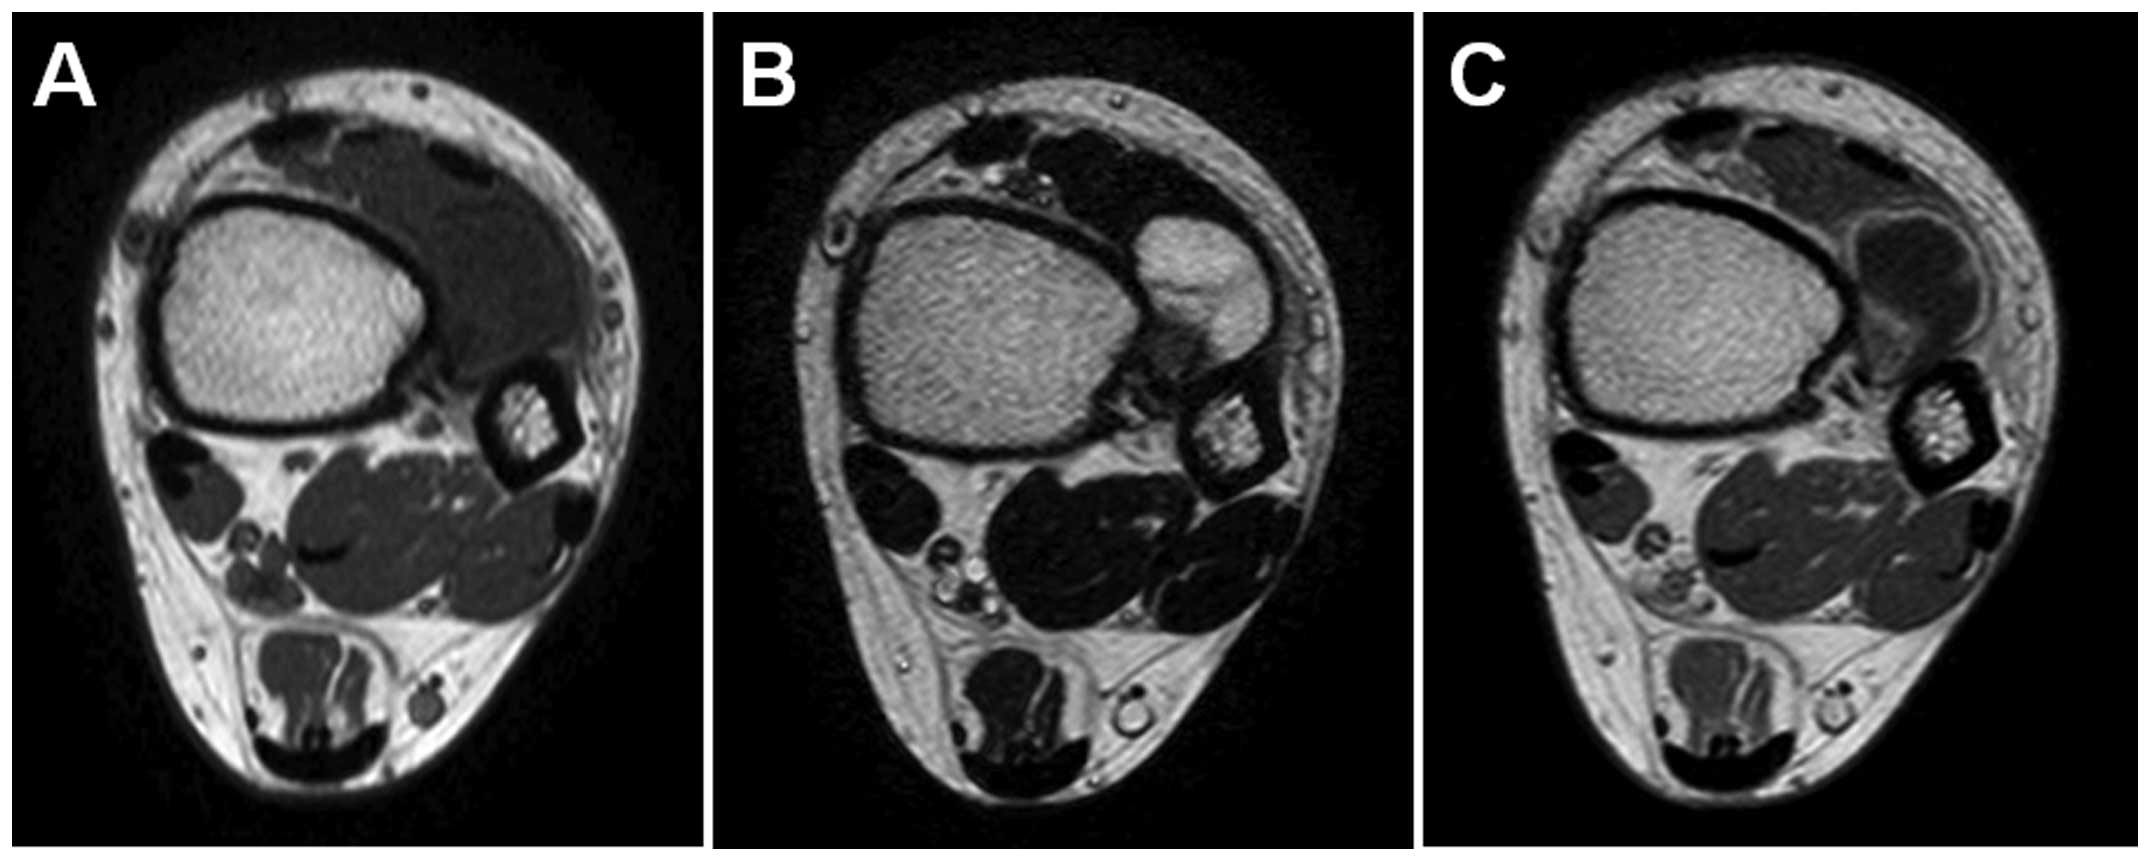

Plain radiographs revealed a discernible soft tissue lesion with peripheral foci of mineralization (Fig. 1). Computed tomography (CT) scans confirmed the presence of a surface-based mass with peripheral ossification and a thin rim of calcification (Fig. 2). Magnetic resonance imaging (MRI) revealed a well-circumscribed juxtacortical mass measuring 2.5×1.8×1.5 cm. The mass exhibited intermediate signal intensity on T1-weighted sequences (Fig. 3A) and high signal intensity with foci of decreased signal intensity on T2-weighted sequences (Fig. 3B). Contrast-enhanced T1-weighted sequences demonstrated predominantly peripheral enhancement without intramedullary involvement (Fig. 3C). Soft tissue edema adjacent to the lesion was also observed.

Figure 3.

Axial magnetic resonance imaging showing a well-circumscribed juxtacortical mass with (A) intermediate signal intensity on T1-weighted sequence and (B) high signal intensity with foci of decreased signal intensity on T2-weighted sequence. (C) Contrast-enhanced T1-weighted sequence demonstrating predominantly peripheral enhancement. No intramedullary extension or edema was identified.

Plain radiographs commonly reveal a discernible soft-tissue lesion with cortical scalloping, underlying cortical sclerosis and overhanging margins (2,5). The lesion may exhibit a sclerotic rim or thin cortical shell. CT is useful in identifying the presence of scattered mineralizationS. On MRI, periosteal chondroma typically appears as a well-circumscribed mass with intermediate signal intensity on T1-weighted sequences and high signal intensity with variable low signal intensity foci on T2-weighted sequences (2,5,6). Intramedullary involvement is quite uncommon, although surrounding soft-tissue edema may occasionally be observed (5). Periosteal chondroma demonstrates predominantly peripheral enhancement following contrast agent administration (6). In our case, the tumor was <3 cm and arose on the surface of the distal tibia. The imaging characteristics were consistent with those described in the literature.